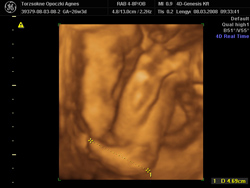

kis keze

kis keze

kis lába

kis lába